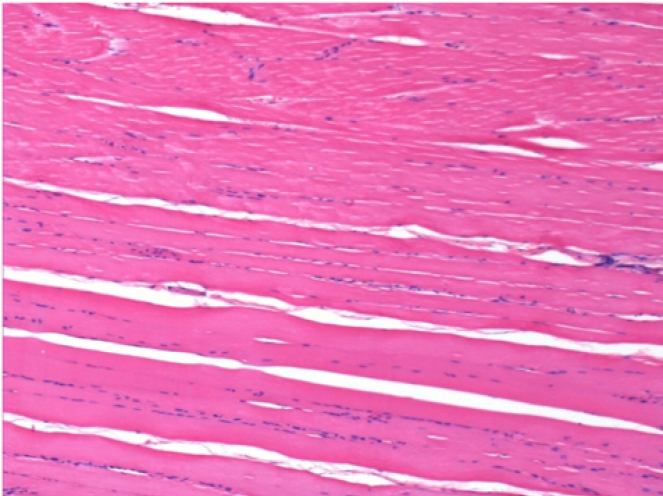

Control

Comentario: Nada que declarar después de la inyección de solución salina.

L: Pretibial-Sin tratamiento

R: Pretibial-Después de 0,1 ml de NaCl 0,9% IM